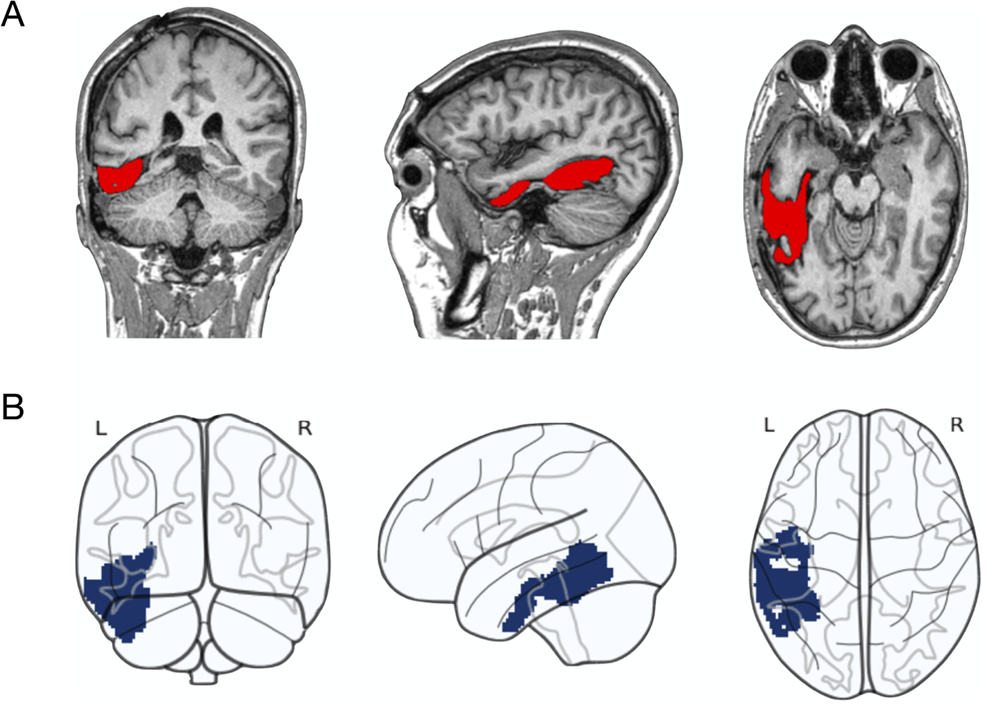

Este marco conceptual sirvió de base para un estudio reciente publicado en Neurobiology of Language por Esti Blanco-Elorrieta y Miren Arantzeta. Analizaron a una hablante nativa de euskera y castellano que, tras un ictus, desarrolló afasia anómica: un trastorno en el que el pensamiento y la comprensión permanecen intactos, pero el acceso a las palabras está alterado. La paciente sabía perfectamente lo que quería decir y podía describirlo o rodearlo con otras palabras, pero no encontraba el término exacto: como si el concepto estuviera ahí, pero la “puerta léxica” estuviera temporalmente cerrada. La lesión afectaba principalmente al giro temporal inferior y al fusiforme izquierdos, regiones clave para el acceso léxico, lo que convertía este caso en una oportunidad excepcional para examinar cómo propiedades como la frecuencia y la concreción modulan el rendimiento lingüístico.